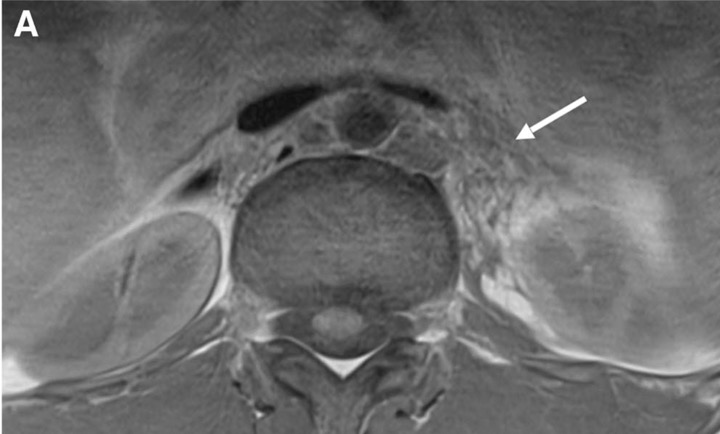

c. Lipomatose encéphalocraniocutanée (ECCL): peau, yeux, SNC)

ECCL: